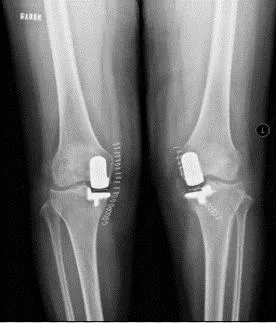

当症状较重影响日常生活,且出现关节畸形和活动受限时,可采取手术治疗。现如今截骨术和膝关节置换术已经时非常成熟且准确的手术,通过手术可解除关节疼痛,大大提升患者的生活质量。

全膝置换术